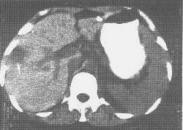

• 肝結核

628健康網為您分享有關肝結核的癥狀,肝結核的治療方法,肝結核的預防知識,肝結核的癥狀圖片,肝結核吃什么藥,肝結核怎么治...